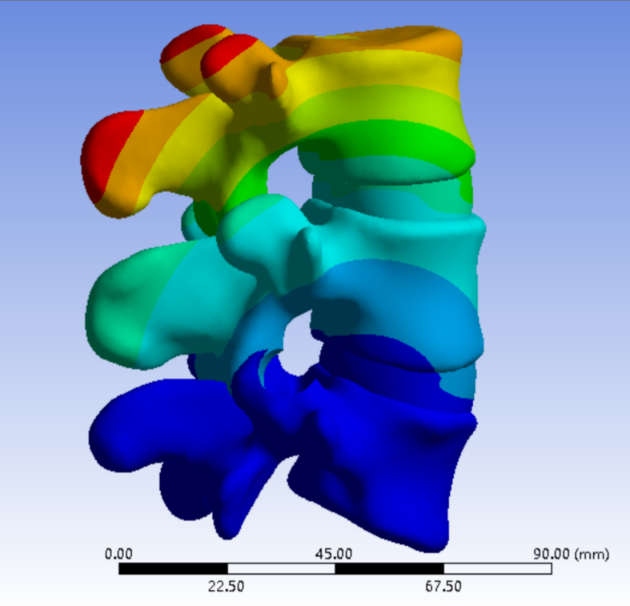

为解决以上问题���,我们提出“椎间孔镜按需成型5级法”��,即将椎间孔镜术中椎间孔成型的实际操作范围进行分级���:0级����:不成型����,见图 1��;1级���:软组织成型�����,只去除关节囊等部分软组织�����,基本不做骨性成型���,见图 2���;2级�����:少许骨质成型���,但不显露下关节突关节面����,见图 3����。3级成型�����:上关节突尖部或上1/2去除成型���,显露下关节突关节面���,见图 4�����;4级成型����:上关节突大部分成型或伴有部分椎弓����、峡部或下关节突小部分���,但预留基底部一部分��,见图 5��。

图 5 4级成型 |

2���、建立五级成型的有限元模型

正常腰椎模型命名为M0���;0级成型为M1��:不做骨性成型���;1级成型为M2���:软组织成型����,只去除关节囊等部分软组织���,基本不做骨性成型��;2级成型为M3����:少许骨质成型��,不显露下关节突关节面����;3级成型为M4a与M4b���:上关节突尖部(M4a)或上1/2(M4b)去除成型���,显露下关节突关节面����;4级成型为M5�����:上关节突大部分成型或伴有部分椎弓���、峡部或下关节突小部分�����,但预留基底部一部分���,见图16-20���。每组模型都按照前屈����、后伸���、左屈����、右屈���、左旋及右旋6种状态加载��,其他约束条件不变���,观察各组成型对于腰椎活动度及椎间盘应力的影响���。

图 20 4级成型 |